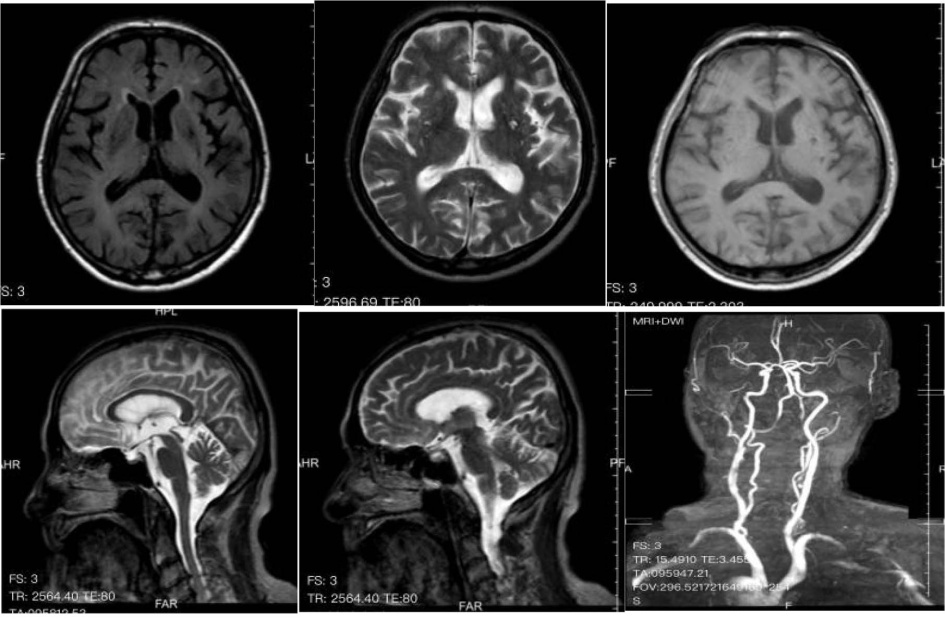

头颅MRI + MRA:右侧椎动脉起始段、远段血流信号减弱;左侧颈总动脉起自头臂干;左侧颈总动脉分叉处、右侧颈内动脉C1段狭窄;多发性脑梗死、软化灶;脑白质脱髓鞘(图4)。

Figure 4. MRI (Magnetic Resonance Imaging) results of the brain

4. 头颅磁共振检查结果

影像学检查在多抗体阳性AE中常缺乏特异性。本例患者头颅MRI仅显示多发性脑梗死和脑白质脱髓鞘,未出现抗NMDAR脑炎常见的颞叶内侧高信号或抗GABABR脑炎的单侧/双侧颞叶异常[9]。这种“影像学阴性”表现约见于20%的多抗体阳性病例,可能与抗体对神经元功能的可逆性干扰而非结构性破坏有关[10]。胸部CT提示的左肺下叶占位及纵隔淋巴结肿大,结合神经元特异性烯醇化酶(94.24 ng/mL)和胃泌素释放前肽(>5000.00 pg/ml)的显著升高,高度提示SCLC的可能,而胸壁肿物病理检出的鳞状上皮细胞进一步支持恶性肿瘤的诊断[11]